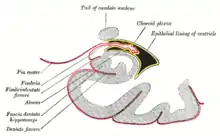

The blood-brain barrier (BBB) is one critical example of protection which prevents toxins and other adverse compounds from reaching the brain.[22] As the brain requires nutrient entry and waste removal, it is perfused by blood flow. Blood can carry a number of ingested toxins, however, which would induce significant neuron death if they reach nervous tissue. Thus, protective cells termed astrocytes surround the capillaries in the brain and absorb nutrients from the blood and subsequently transport them to the neurons, effectively isolating the brain from a number of potential chemical insults.[22]

This barrier creates a tight hydrophobic layer around the capillaries in the brain, inhibiting the transport of large or hydrophilic compounds. In addition to the BBB, the choroid plexus provides a layer of protection against toxin absorption in the brain. The choroid plexuses are vascularized layers of tissue found in the third, fourth, and lateral ventricles of the brain, which through the function of their ependymal cells, are responsible for the synthesis of cerebrospinal fluid (CSF).[23] Importantly, through selective passage of ions and nutrients and trapping heavy metals such as lead, the choroid plexuses maintain a strictly regulated environment which contains the brain and spinal cord.[22][23]